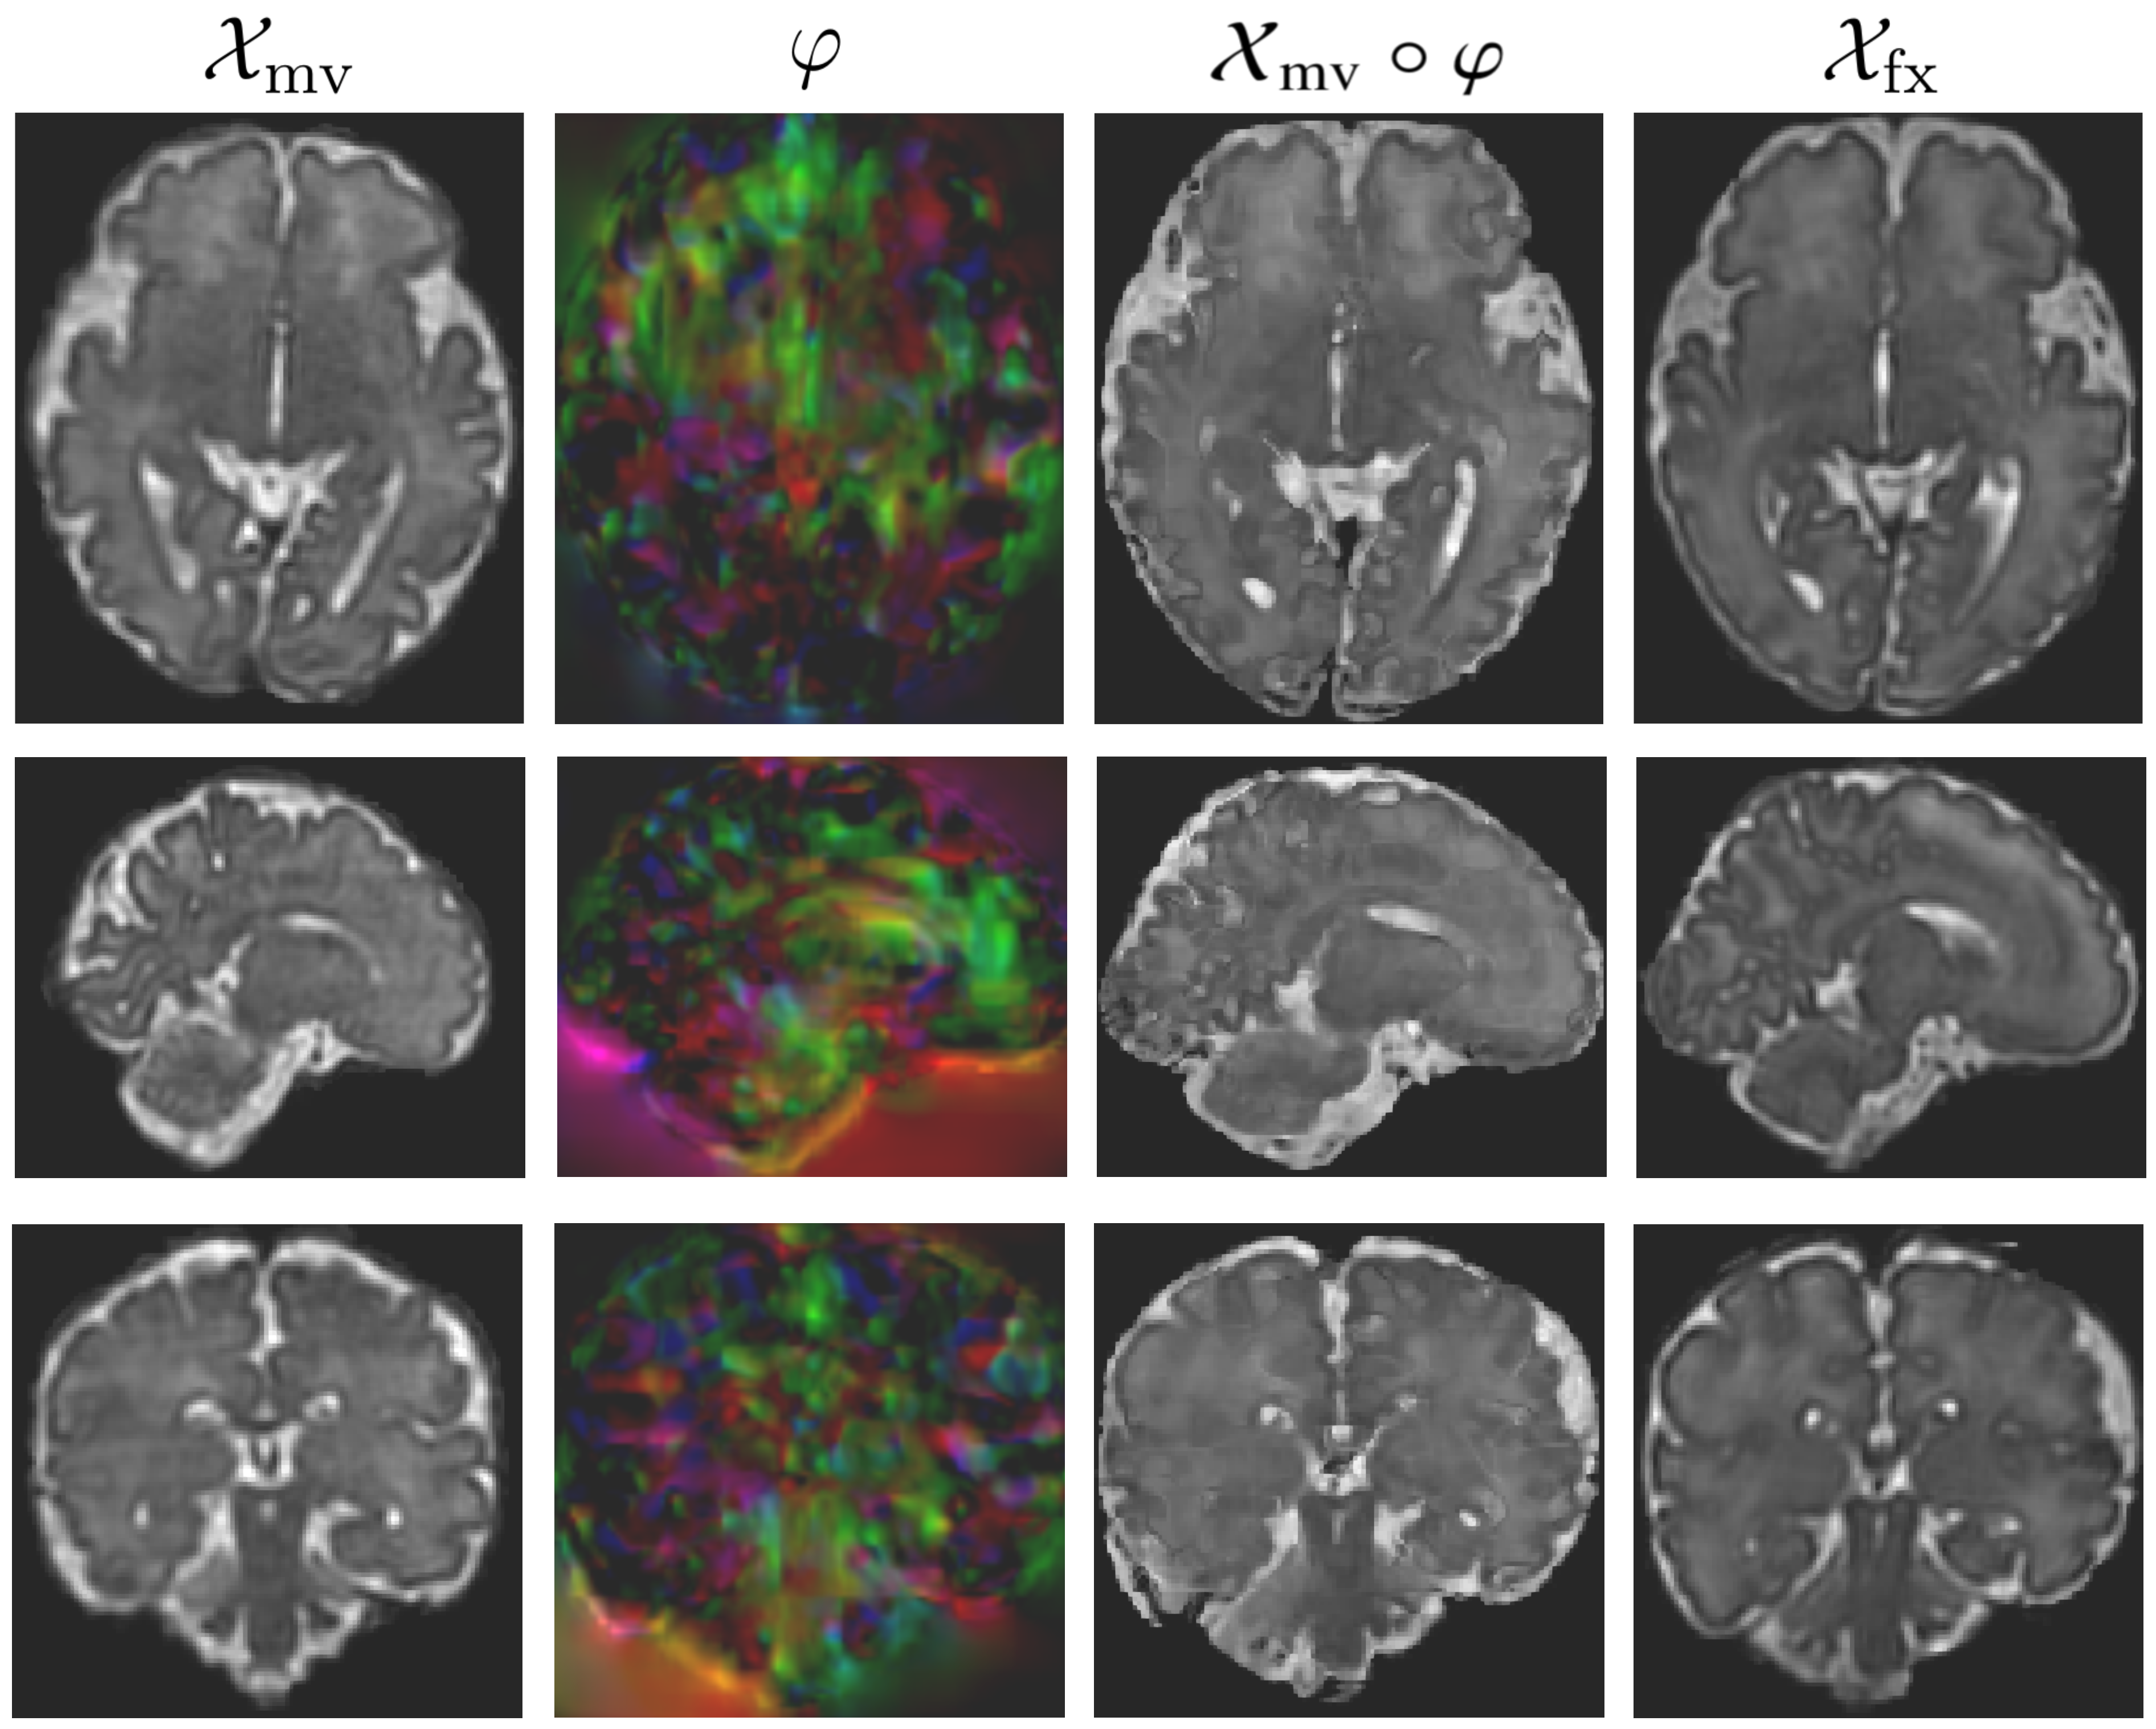

A comparison of the qualitative results of our method with VoxelMorph [3] is shown in Figure 5. It clearly establishes that the cascaded registration produces better and more realistic results. The appearance of the deformation field is also substantially different for both methods. This is due to the fact that the cascaded approach computes the deformation fields at different scales, rather than a single, global deformation field. Hence, the final deformation field is able to capture more accurately the local variations in the shape and structure of the fixed image.